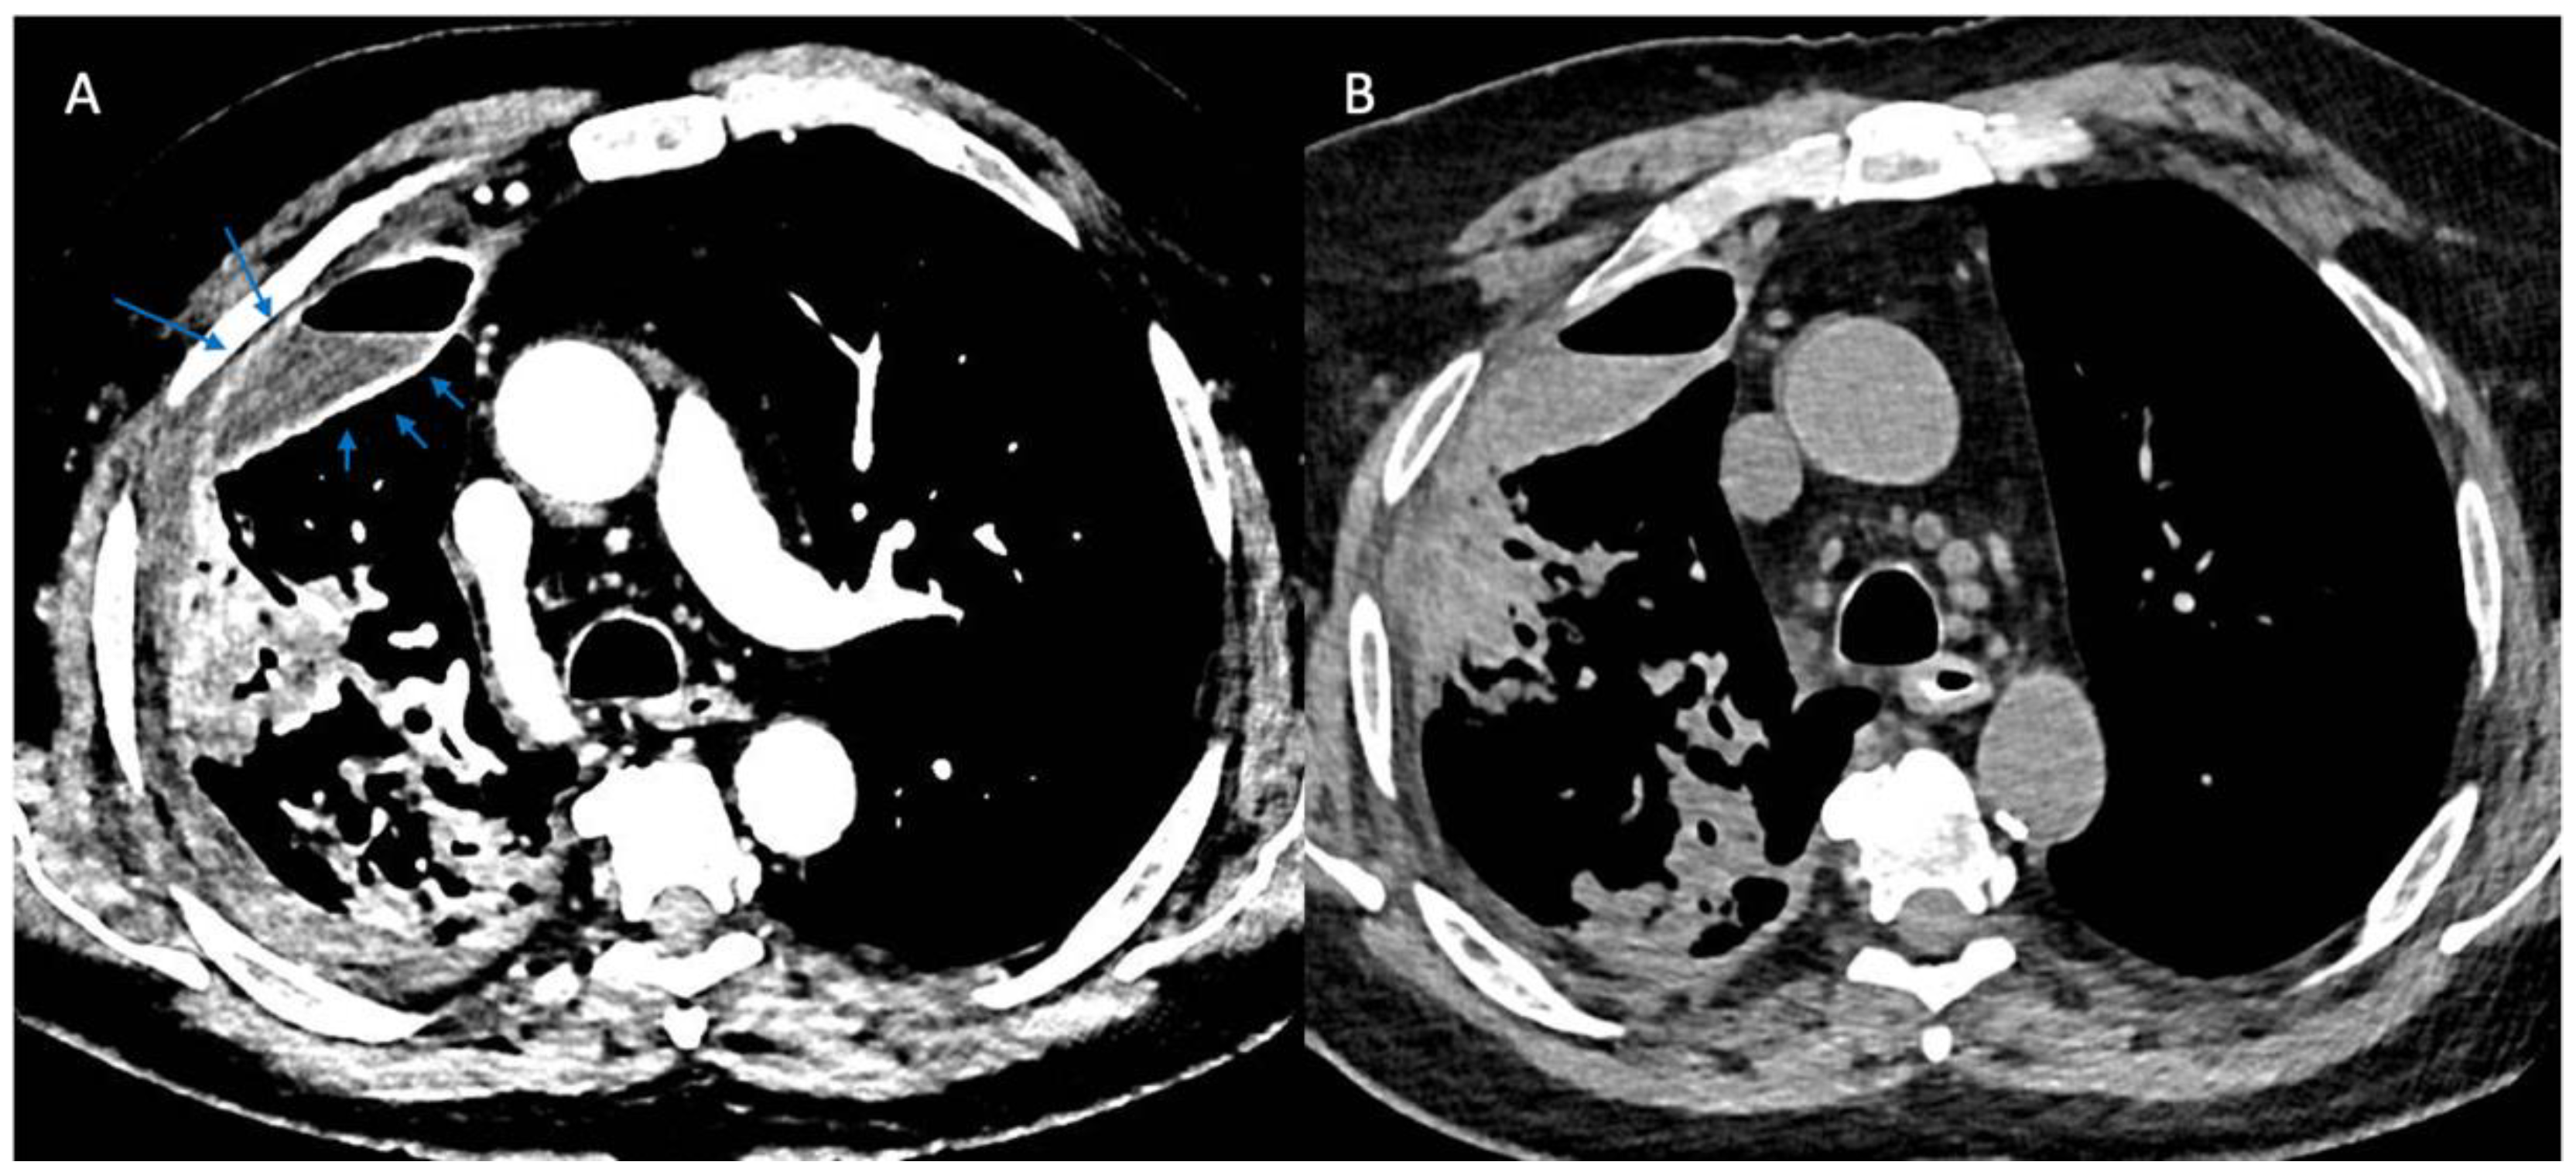

More recently, computed tomographic imaging has proven useful in the radiographic assessment of empyema as it allows for a more thorough investigation of lung parenchyma, pleura, and extrapleural fat abnormalities. The organizing phase of complicated pleural infections is characterized by fibrin deposition on the visceral and parietal pleura with associated ingrowth of capillaries and fibroblasts. This forms the basis for pleural thickening and the split pleura sign (Figure 2) that was originally reported in 68% of CT scans in patients with empyema and was later found to be present in 98.7% of patients with pleural infection who underwent pleural phase contrast-enhanced CT [24], [25]. Furthermore, the presence of a split pleura sign with a total pleural fluid thickness of >30 mm was found to be 79.4% sensitive and 80.9% specific for distinguishing complicated parapneumonic effusion and empyema from non-complicated parapneumonic effusion [26]. More recently, Porcel et al. used multivariate regression analysis to generate a simple scoring system for patients with pleural infection who underwent pleural enhanced CT scan and found that it was also useful in separating non-complicated parapneumonic effusions from complicated parapneumonic effusions that required mechanical drainage. Specifically, a total of four points when combining the presence or absence of pleural contrast enhancement (3 points), pleural microbubbles (1 point), increased attenuation of extrapleural fat (1 point), and pleural fluid volume ≥ 400 mL (1 point) were shown to be 84% sensitive and 75% specific with a positive and negative likelihood ratio of 3.4 and 0.22, respectively, for differentiating complicated from non-complicated parapneumonic effusions [27].

Figure 2.

Split Pleura Sign. Panel (A) shows contrast enhancement of both the visceral and parietal pleura (arrows) in a patient with empyema (windowing optimized to show pleural enhancement). Panel (B) shows a non-contrast study in the same patient several days prior. Comparison of the two images demonstrates the value of contrast when evaluating patients with suspected pleural space infections.